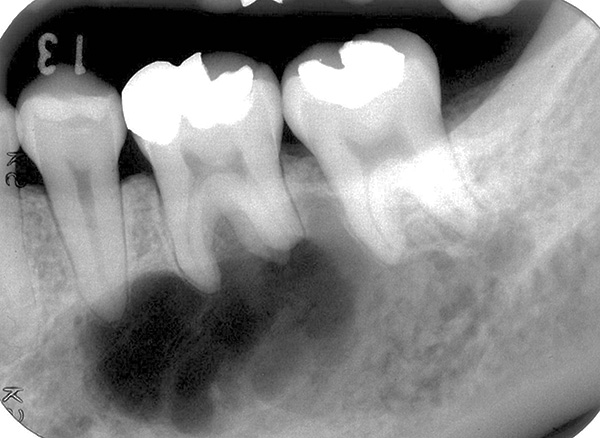

A foto abaixo mostra um exemplo de um cisto enorme, que não foi removido em tempo hábil e, tendo aumentado em volume, cresceu até as raízes de um dente adjacente:

É difícil determinar com uma imagem objetiva e mesmo com uma tomografia computadorizada com 100% de precisão que forma do processo inflamatório está presente na (s) raiz (s) do dente. Área de iluminação geralmente visível com contornos claros, geralmente arredondados ou ovais. Esse "círculo" pode ser localizado não apenas em uma raiz, mas também captura 2-3 raízes de um dente e até mesmo passa nas proximidades imediatas do topo das raízes dos dentes adjacentes, sugerindo ao dentista a escala da tragédia.

- O tamanho grande do cisto, quando cria sérios riscos para as raízes dos dentes adjacentes;